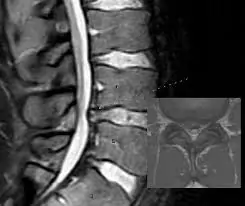

મોબિલિટી એક્સરસાઇઝ (Mobility exercises) આધુનિક ફિટનેસ અને રિહેબિલિટેશન (પુનર્વસન) દિનચર્યાઓનો એક આવશ્યક ભાગ બની ગઈ છે. ભલે તમે રમતવીર હોવ, ફિટનેસના શોખીન હોવ અથવા બેઠાડુ જીવનશૈલીને કારણે જડતાનો સામનો કરી રહ્યાં હોવ, તમારી ગતિશીલતા (mobility) સુધારવાથી તમારા જીવનની એકંદર ગુણવત્તામાં નોંધપાત્ર વધારો થઈ શકે છે. સાચા અર્થમાં ફક્ત સ્ટ્રેચિંગ કરવા કરતાં અલગ, મોબિલિટી એક્સરસાઇઝ સાંધાની…